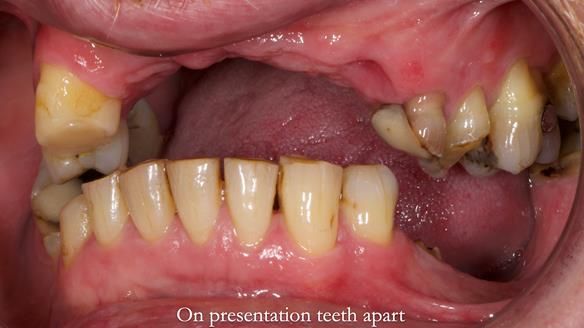

Keith’s combat denture case study

Keith’s case was one of the most challenging and rewarding cases I’ve treated this year. This 64 year old man presented with ill-fitting acrylic partial dentures that lacked stability, retention, and aesthetics. They constantly broke. He had lost the upper front teeth in a road traffic accident in his early 20s. The unopposed teeth had erupted, taking up space. After careful planning, we made a durable, metal-based upper partial denture/splint to address his dental concerns. He loved the outcome.

I also used the Dahl concept to re-establish the occlusion upon fitting the RPD, which helped to intrude the lower left canine without needing to grind it too much.